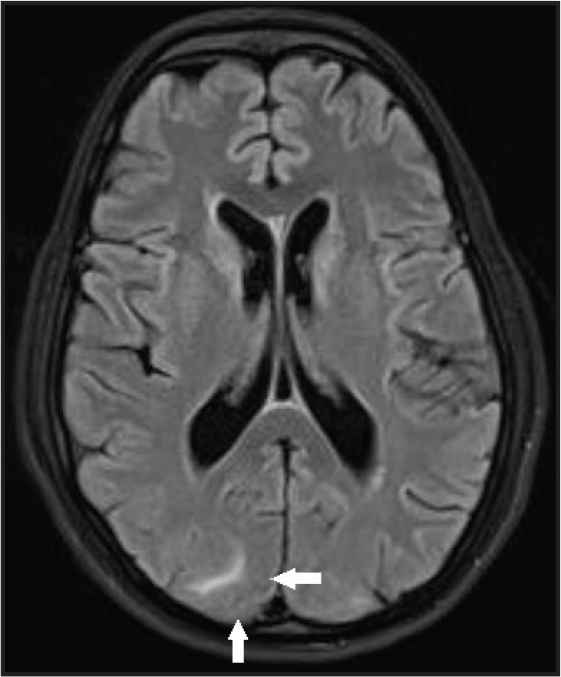

Her immediate post-operative haemoglobin was 8.5 gm% and platelet count was 1.5 lakhs but haematuria persisted. She therefore received fresh frozen plasma 25 ml/kg body weight 8th hourly and intravenous fluids at 20 ml/h and intravenous furosemide 40 mg 12 hourly. She was started on intravenous piperacillin 4.5 g 12 hourly, amikacin 375 mg once daily and metronidazole 500 mg 8 hourly. Bedside X-ray chest showed features of pulmonary oedema and aspiration especially on right side (Figure 1A). Echocardiogram (ECHO) showed left ventricular diastolic diameter of 4.4 cm, global hypokinesia of left ventricle with ejection fraction of 45%. She was started on tablet enalapril 2.5 mg through ryles tube. Hypertensive crisis was managed by Nitroglycerine (NTG) infusion and dose titration done to keep the Mean Arterial Pressure (MAP) at 90–100 mmHg. Fundus examination showed grade 2 hypertensive retinopathy and there was no papilledema. Magnesium sulphate 1 g/h infusion was started on post-operative day 1. After 48 h she regained consciousness after stopping Midazolam infusion. Hypertensive crisis recurred (160/117 mmHg) despite NTG infusion. Intravenous labetalol 20 mg was given and she was sedated with midazolam again as she was restless due to the endotracheal tube block and leakage which was identified and rectified. Abdominal gaseous distension was managed by inserting dulcolax rectal pessary. Nitroglycerine was ceased after BP stabilised at 120/70 mmHg. She subsequently received oral. Amlodipine 5 mg 12 hourly, enalapril 2.5 mg 12 hourly and oral aldactone (Spiranolactone) 25 mg once daily through ryles tube. She continued to receive intravenous hydrocortisone 100 mg once daily for 3 days. She was extubated on third post-operative day and continued on nasal oxygen 4–6 L/min and Furacort (Formoterol Fumarate Dihydrate) nebulisation 8 hourly for 1 week along with chest physiotherapy. Her follow-up ECHO on third day of intensive care stay showed an improved ejection fraction (52%) and mild global hypokinesia. Chest X-rays repeated on third and sixth day of intensive care stay (Figure 1B and 1C) showed improvement in lung fields. CT brain done on fifth post-operative day (Figure 2) showed features of frontal lobe and occipital lobe oedema suggestive of PRES which was confirmed by MRI brain performed 2 days later (Figure 3).

MRI brain: white matter vasogenic oedema in occipital lobe confirmation of PRES

Mortality in eclampsia is due to the complications like aspiration, cerebrovascular accident, pulmonary oedema and abruption. Sudden cardiac arrest is a rare event and is diagnosed by the absence of pulse or heart beat on auscultation within 1 h of convulsive episode [4] Cardiopulmonary arrest in pregnancy is rare occurring in one in 30,000 pregnancies and only 50% survival [3]. Pulmonary oedema occurs in 2.9% of all severe pre-eclampsia and eclampsia [5] and 30% occur in the antepartum period [6]. Posterior reversible encephalopathy syndrome (PRES) occurs in more than 90% of women with eclampsia [7] and it can be predicted in young women with hypertensive crisis, thrombocytopenia and proteinuria [8]. The clinical manifestations of PRES include headache, altered mental status, loss of consciousness and seizures. Typical findings on MRI are vasogenic oedema with T2 hyperintensities in the posterior subcortical and white matter of occipital lobes.